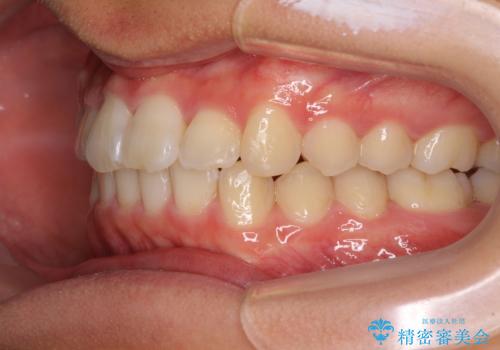

- 八重歯を気にして来院された高校生の患者様です。

ボディーコンタクトの激しい部活動を行っているため、補助装置とインビザラインを用いて、部活動を継続しながら治療を行うこととしました。

八重歯を効率よく改善するため、補助装置を使用して上顎の奥歯を後方に移動させました。

部活動をしながらでしたが、マウスピースをしっかりと装着してくださったので、1年半程度で終了することができました。